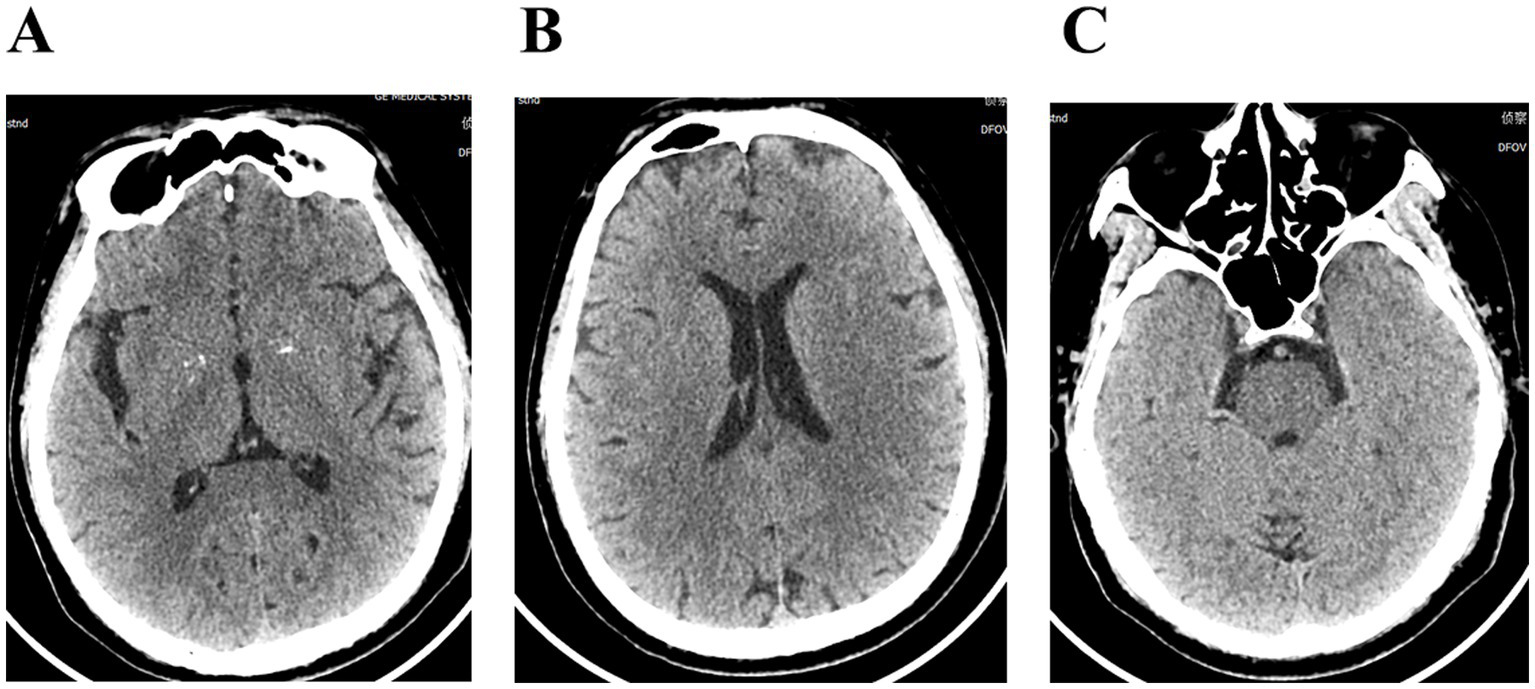

Figure 2

(A–C) Cranial computerized tomography showed no significant abnormalities.

The patient, a 58-year-old male farmer, was admitted to the hospital on November 08, 2023, due to “numbness and weakness of the right upper limb for 2 days, aggravated for 1 day.” On October 14, 2023, he was bitten by an unregulated, unvaccinated domestic dog on the back of the right hand, resulting in penetrating injuries and bleeding (Figure 1). The wounds were simply washed and disinfected, and the treatment of wounds was not standardized. There was no passive immunization against rabies, and only the freeze-dried rabies vaccine (Liaoning Chengda Vero) was routinely administered. According to the “2-1-1” immunization program, two doses of rabies vaccine were injected on the day 0 (1 dose for each of the deltoid muscles of the left and right upper arms), followed by one dose on the day 7 and 21, respectively. The classification of rabies exposure based on the mode of exposure and degree of exposure is categorized as class III exposure. The patient displayed with weakness and numbness in the distal right upper extremity starting 23 days after the canine injury. The weakness primarily affected the distal of the right upper limb, initially manifesting as mild characterized by an inability to perform fine motor movements, and was accompanied by neck and shoulder pain, nausea, vomiting. On the day 24, the weakness and numbness in the distal right upper limb progressively worsened, accompanied by fever with a maximum temperature of 38.8 °C. There were no signs of slurred vision, visual field defects, or gibberish. Furthermore, there were no indications of slurred speech, difficulties in swallowing, or choking on water. The patient was admitted to the outpatient clinic and later to the hospital for “acute cerebral infarction” after an emergency computerized tomography (CT) scan that showed no abnormalities (Figure 2). There was a denial of any recent infections. The patient also denied any previous cerebrovascular disease risk factors such as hypertension, diabetes mellitus, coronary artery disease, hyperlipidemia, and hyperuricemia; however, there was a history of epilepsy. The patient received three complete doses of COVID-19 vaccine beginning June 1, 2021.